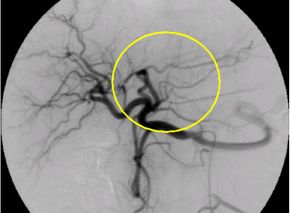

肝細胞がんに対する経カテーテル動脈化学塞栓療法の実際

大腿動脈(太ももの付け根の血管)又は上腕動脈の位置を確認し、消毒と局所麻酔を行い

ます。動脈を正確に穿刺してカテーテルを挿入し慎重に進めていきます。肝細胞がんを

栄養する血管が同定できたら、マイクロカテーテル(通常ものよりさらに細いカテーテル

)を栄養血管へ選択的に挿入し、腫瘍の近傍まで進め、そこから造影を行います。

次に肝細胞がんの径、腫瘍濃染、患者さまの全身状態、肝臓機能などを総合的に判断し

、マイクロカテーテルか治療後の造影では塞栓物質により肝細胞がんへの血流がなくな

っているので腫瘍は描出されません。

肝細胞がんを栄養する血管描出(塞栓前) 肝細胞がんを栄養する血管描出(塞栓後)

選択的動脈造影 上腸間膜動脈造影